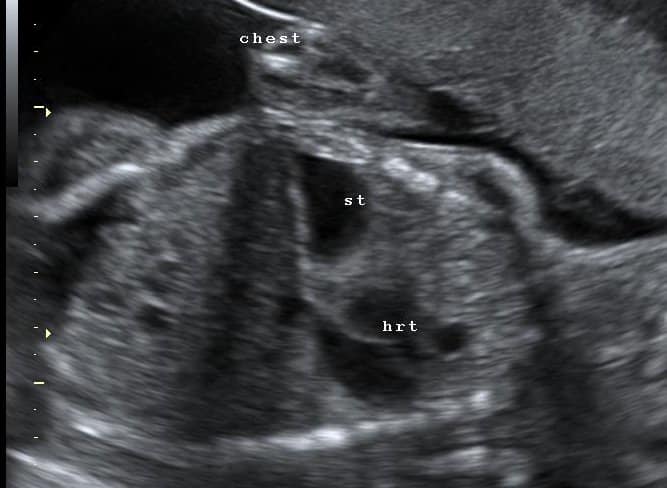

Fig 3 - Ultrasound scan of diaphragmatic hernia - a cause of polyhydramnios. The stomach (st) and heart (hrt) are both within the thorax.

Fig 3

Ultrasound scan of diaphragmatic hernia – a cause of polyhydramnios. The stomach (st) and heart (hrt) are both within the thorax.